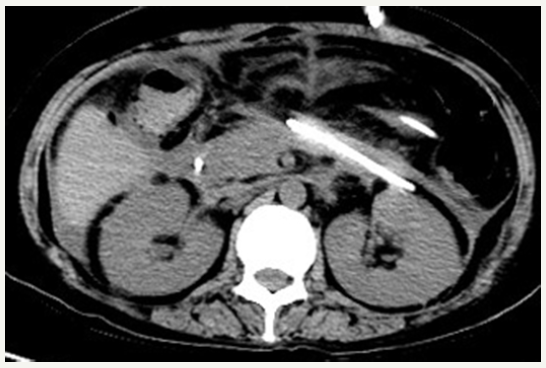

Figure 4:CT scan showing the disappeared pancreatic pseudocysts.

She recovered well after operation. The pancreatic pseudocysts gradually reduced (Figure 4). The symptom of pyrexia disappeared by repeat lavage through the drainage tube and the use of antibiotics. Her general condition improved and left our hospital on August 20.